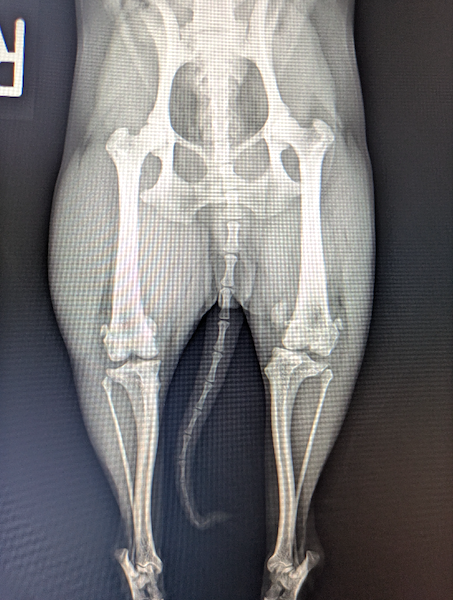

膝蓋骨脱臼は、小型犬に多く見られる運動器の病気です。膝のお皿が内側に外れる場合を内方脱臼、外側に外れる場合を外方脱臼と言いますが、内方脱臼の方が発生が多いことが知られています。症状としては、脱臼する側の後ろ足をあげる、足を地面に上手に着くことができないなどの歩行異常を認めます。この病気は自然に改善することはなく、特に成長期に病態が進む特徴があります。脱臼が頻繁に生じ、歩行異常や痛みの症状を認める場合、治療には骨格を矯正する外科治療が必要です。歩き方や座り方がおかしいなと感じる場合はお早めにご相談下さい。

獣医師 臼井